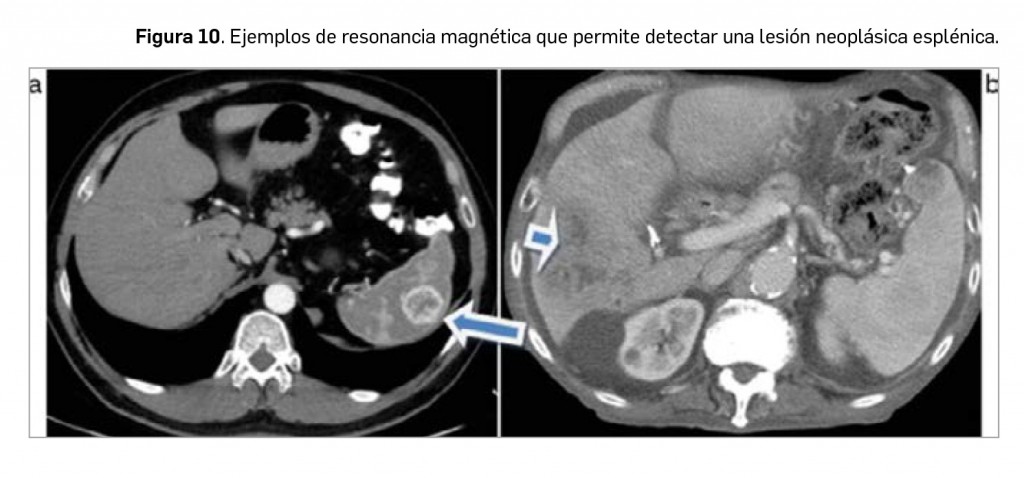

El diagnóstico diferencial de las lesiones esplénicas es amplio, dada la gran variedad de formas de afectación del bazo, siendo, la gran mayoría de las lesiones de apariencia inespecífica, difíciles de comprobar histológicamente. Por tanto, se hace necesario considerar el contexto clínico del paciente en el que se detecta una lesión o una anomalía esplénica.

Por otro lado, las lesiones focales esplénicas primarias son, en su gran mayoría, benignas, y salvo los quistes o hemangiomas, suelen presentar un comportamiento poco específico. Las más frecuentes presentan unas características de imagen que permiten realizar un diagnóstico de aproximación. Una lesión focal esplénica aislada en un paciente con cáncer, pero sin enfermedad metastásica diseminada, no suele corresponderse a una metástasis.